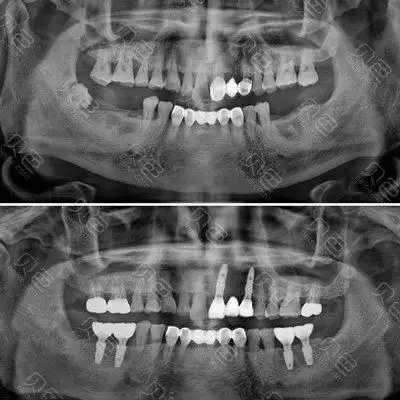

种植牙术前术后拍片对比

吴女士种植带冠后的牙片显示,种植体就位精准,受力均衡